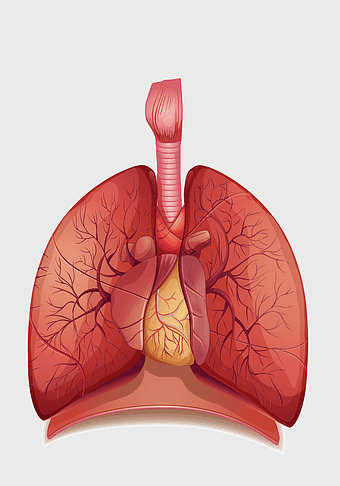

human lung anatomy, respiratory system illustration, heart and lungs diagram, bronchus structure, pulmonary function, thoracic cavity, medical imaging analysis -